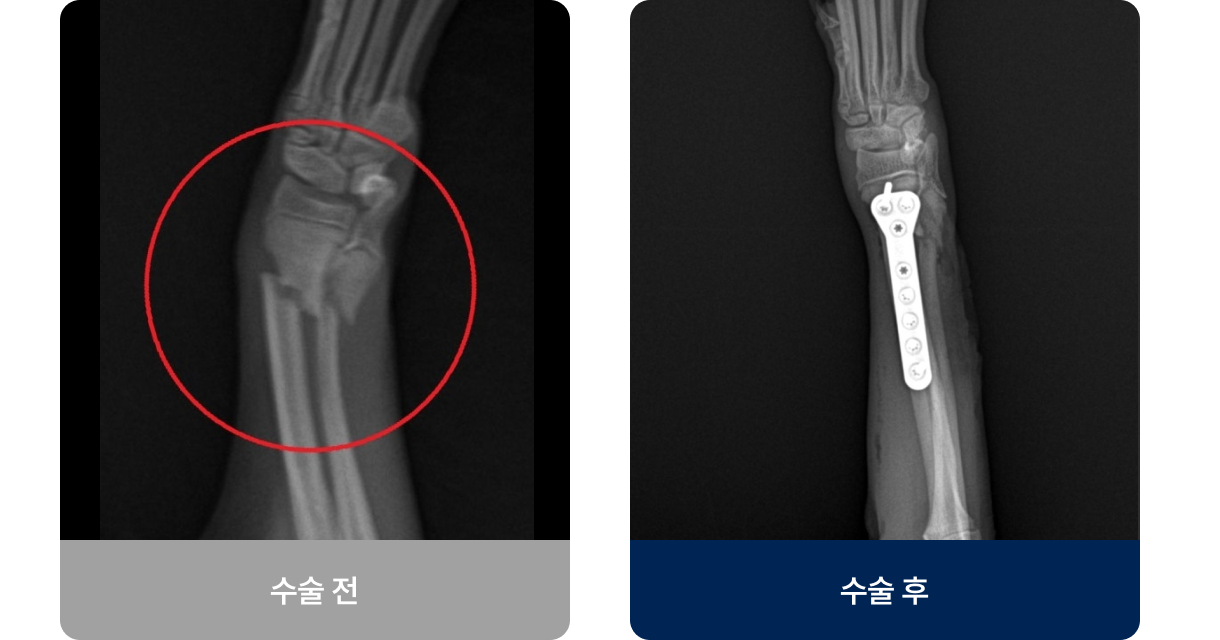

뼈의 연속성이 끊어진 상태로, 충격(낙상·교통사고)이나 병적 요인으로 발생합니다. 갑자기 다리를 절고 신음소리를 내거나 움직이지 않고 일어서거나 걷지 못하는 증상을 보입니다. 대부분 수술이나 깁스 고정을 통해 치료 후, 일정 기간의 휴식과 재활치료를 통해 근력과 관절 운동을 회복해야 합니다.

외과적 치료법(수술적 치료)

수술법은 골절 부위·형태·체중에 따라 달라지지만, 현재 플레이트 고정술이 가장 널리 사용되고 있습니다.